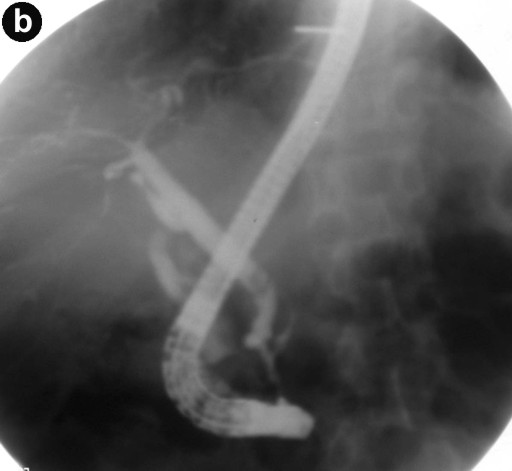

The most common findings on imaging were bulky pancreas with loss of lobulations and common bile duct stricture, and the majority (4/5) underwent common bile duct stenting (Figures 2 and 3). IgG4 serology was carried out in 4 of the 5 patients and it was positive in 3 of them. Two of the patients had extrapancreatic manifestations in the form of hypodense lesions in the kidney (2/5) and mediastinal lymphadenopathy (1/5). All patients were treated with prednisolone 40 mg/day for 4 weeks followed by a tapering off of 5 mg per week over the next 7 weeks; all of them showed rapid clinical improvement. Follow-up liver function tests showed resolution of hyperbilirubinemia and a decrease in serum alkaline phosphatase. Patients with common bile duct stricture underwent repeat ERCP and their cholangiograms showed resolution of the stricture following therapy with steroids (Figure 3). There was no recurrence after a follow-up of 6-8 months.

Figure 3. a. ERCP image prior to treatment shows a long segmental smooth stricture at the terminal end (long arrow) with a dilated common bile duct. There is another tight stricture at confluence involving both right and left biliary ducts (small arrow) with dilated biliary radicals in both lobes of the liver. b. Post-treatment ERCP image shows resolution of the strictures with a common bile duct of normal caliber and non-dilated biliary radicals. |

Imaging findings suggestive of autoimmune pancreatitis are the presence of focal or diffuse enlargement of the gland (sausage-shaped) with loss of lobulations with or without a capsule-like rim and the absence of vascular encasement or calcification [23, 24, 25]. Extrapancreatic manifestations are quite common in autoimmune pancreatitis and, if present, can aid in strengthening the diagnosis. The biliary tract is the most common extrapancreatic system to be involved in autoimmune pancreatitis (30-90%). Both intrahepatic and extrahepatic bile ducts can be affected; however, the distal common bile duct is the most common site of involvement [23, 24, 25]. Renal involvement is also common (35%) in the form of multiple small hypoattenuating peripheral cortical rounded wedge-shaped nodules [26]. Other extrapancreatic manifestations in autoimmune pancreatitis include hilar lymphadenopathy, lacrimal and salivary gland involvement and retroperitoneal fibrosis [24, 25]. The hallmark finding on ERCP in patients with autoimmune pancreatitis is a focal, diffuse or segmental attenuation of the main pancreatic duct and the disappearance of right-angled branches. The main pancreatic duct adjacent to or upstream of the strictures is minimally dilated. Other common findings on ERCP are the narrowing of the intrapancreatic portion of the common bile duct, irregular narrowing of the extrahepatic bile ducts and, less frequently, enlarged intrahepatic bile ducts [25, 27]. Pancreatographic findings were available in 3 of our patients and they all showed uneven contour and dilatation of the main pancreatic duct.